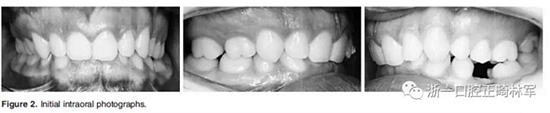

3.體格檢查:直面型,露齦笑,深覆合、合平面傾斜(Figure 1)。上中線偏右3mm,下中線偏左2mm。磨牙II類關(guān)系,左側(cè)尖牙II類關(guān)系,右側(cè)尖牙I類關(guān)系,左下第二磨牙低位咬合,右上前磨牙缺失。覆蓋率為100%,覆蓋度為4mm。咬合平面重度傾斜,左側(cè)向下移位(Figure 2、3)。